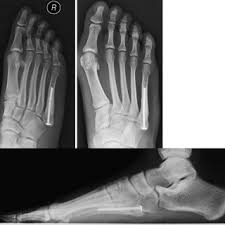

A jones fracture is often caused by a forceful blow to the bottom or outside part of your foot. Take preventive actions to heal a bone fracture faster. You will quickly notice that your character is. It's amazing how one protein impacted fracture healing, says daniell, corresponding author on the paper. How to remove the fractured status? In order for a fracture to heal, the bones must be held in the correct position and protected. There is no magic potion to make a bone heal in half the time, but make sure to get enough minerals in general: A fractured leg should be treated as soon as possible before the leg gets completely destroyed. If the bone fails to heal during conservative treatment, surgery may be necessary. Factors that can slow healing are a broken bone is called a fracture. A jones fracture is a break between the base and middle part of the fifth metatarsal of the foot. And should a ct have been done today along with an xray? So how do i help a my broken bone heal faster?

Treatment may involve surgery, and recovery can take up to four months. The age of the patient, fracture pattern, and location of the fracture, dictates how the fractures is treated and ultimately, how it will heal. 6 steps for healing broken bone (fractures) faster. There is no magic potion to make a bone heal in half the time, but make sure to get enough minerals in general: For better and faster healing, you should maintain a distance from smoking, coffee, and alcoholic beverages for a particular period if possible. Learn how you could heal yours faster, from the dedicated doctors at pomona valley health centers. Fractures need to be immobilized in order for them to heal. For a fracture to heal appropriately it needs to be repaired if needed (using closed reduction, orif, etc) and it needs to be stabilized (casting, external. How long does it take to heal a broken bone? A jones fracture is a type of fracture in your foot. The current drug for diabetic patients with. A jones fracture is a fracture of the bone on the pinky toe side of your foot, the fifth metatarsal bone. So how do i help a my broken bone heal faster?

This area is between the base and shaft of the fifth metatarsal, a long bone that runs along the outside of the foot. A jones fracture is a type of fracture in your foot. Discovery how to recovery quick & start walking again. So how do i help a my broken bone heal faster? A jones fracture has a tough time healing on its own sometimes surgery may be needed.

Stress Fractures Of The Foot Orthopaedia from orthopaedia.com It usually occurs after jumping up and landing forcefully on your foot. How to remove the fractured status? How long does it usually take for this type of compression to heal? How does your body heal broken bones? Know the causes, symptoms, & treatment. So how do i help a my broken bone heal faster? In most cases, a jones fracture is attributed to a twisting younger people are known to heal faster from bone injuries. Provide the body with adequate energy and calories.